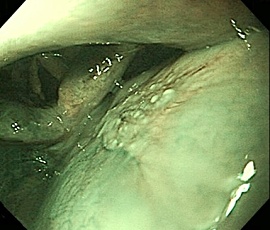

[咽頭腔外魚骨異物] 手術:内視鏡的粘膜下層剥離術(異物除去)

内視鏡画像